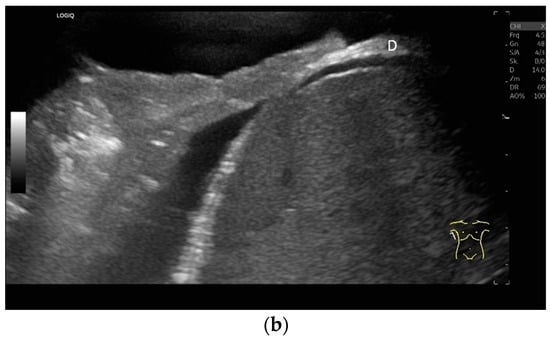

Regardless of the recommended positions for standardized measurements, the diaphragm can be viewed in other areas. This works quite well on the flank and subcostally in the midclavicular line (Figure 7).